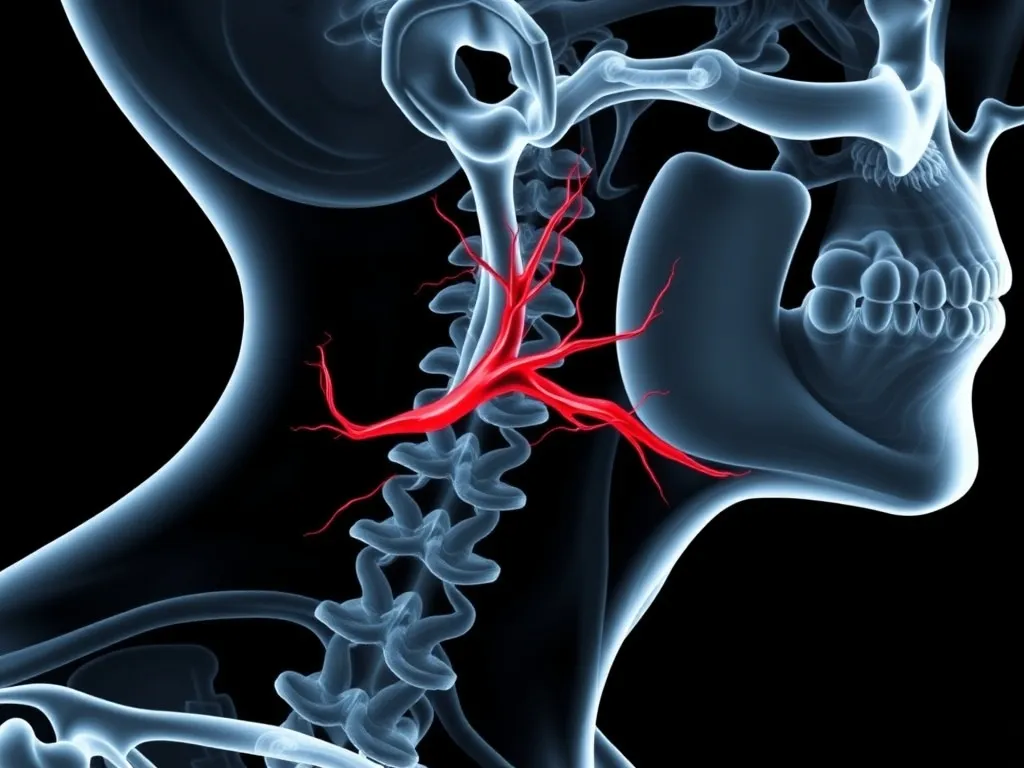

Temporal (Giant Cell) Arteritis